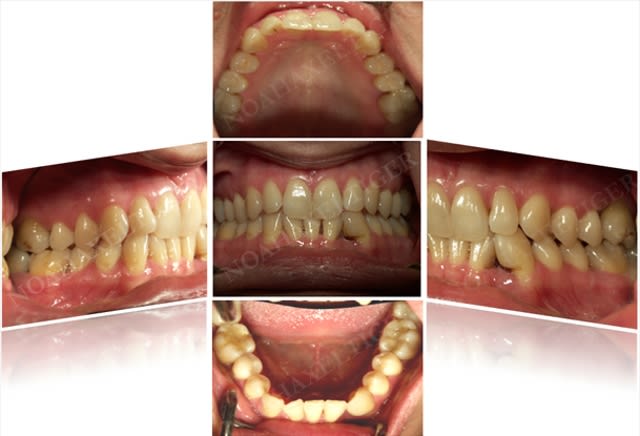

une attaque parodontal maousse.... et absence totale de gencive attachée sur une 35.

voilà à quoi ça ressemble aujourd'hui...

l'absence de 46 ne doit pas beaucoup aider ...enfin moi je dis cela je dis rien

pas de surcharges occlusales sur ta 5 ?? ou d'interference....

il y a un trauma occlusal, à l'évidence. mais le trauma n'est qu'un facteur aggravant.

la patiente est en traitement paro en attendant une réévaluation dans trois à quatre mois.. mais elle est ouverte à tout.